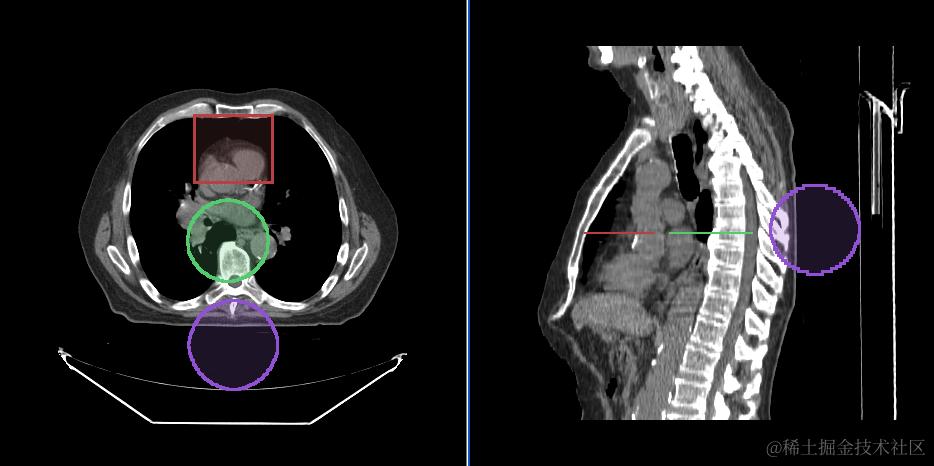

矩形面积的测量和统计(RectangleRoi Tool)

测量椭球体的体积和统计信息(EllipseRoi Tool)